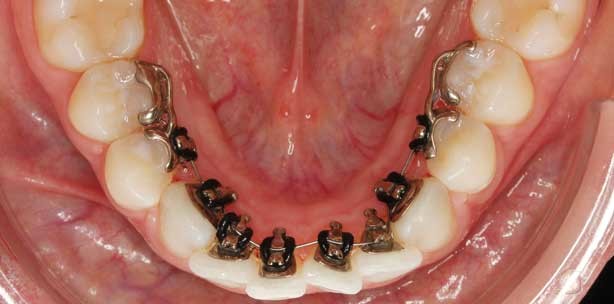

Fall 1 (Abb. 1a–e): Splints auf den UK-Prämolaren

• Diagnose: ausgeprägter frontaler Engstand mit im Drehstand befindlichen Canini

• Maßnahme: IncognitoTM Lite mit Splints auf den Zähnen 34 und 35 sowie 44 und 45

• Bogensequenz: 0.014'' NiTi, 0.016'' x 0.022'' NiTi, 0.0182'' x 0.0182'' Beta III Titanium

• Behandlungsdauer: sechs Monate